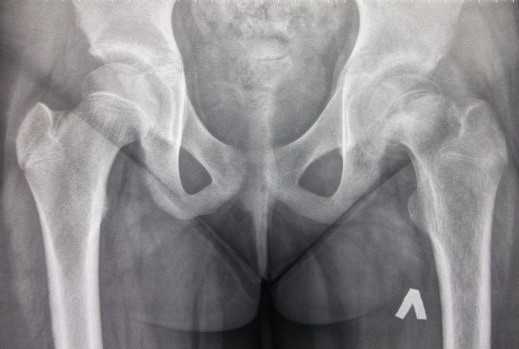

Рентген

Один из основных методов диагностики - рентгенография тазобедренных суставов, которую проводят в двух проекциях. По данным снимков можно обнаружить главные признаки заболевания и поставить правильный диагноз.

На начальных этапах развития определяют рыхлость, размытость очертаний эпифизарной пластины, увеличение ее границ. На эпифизе наблюдаются участки остеосклероза, остеопороза с пятнистой послойной структурой. На поздних стадиях болезни эпифиз головки бедренной кости соскальзывает медиально. На заключительной стадии появляются признаки консолидации перелома, изменение шейки бедра, сужение суставной щели.

Поражение головки бедра диагностируется травматологами-ортопедами на основании жалоб, результатов объективного обследования и визуализационных методик. Основным методом обследования является рентгенография тазобедренного сустава. Процедура выполняется в 2 проекциях, наиболее информативна боковая проекция. Изменения зависят от стадии заболевания.

Сначала ростковый хрящ на рентгеновских снимках расширяется, шейка становится слоисто-пятнистой из-за чередования участков остеосклероза и остеопороза. Затем обнаруживается прогрессирующее смещение головки, после этого просматривается линия перелома. На заключительной стадии выявляются признаки консолидации перелома, ремоделирование шейки бедра, сужение суставной щели.